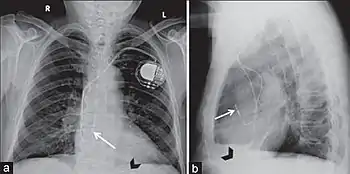

Permanent pacing with an implantable pacemaker involves transvenous placement of one or more pacing electrodes within a chamber, or chambers, of the heart, while the pacemaker is implanted under the skin below the clavicle. The procedure is performed by incision of a suitable vein into which the electrode lead is inserted and passed along the vein, through the valve of the heart, until positioned in the chamber. The procedure is facilitated by fluoroscopy which enables the physician to view the passage of the electrode lead. After satisfactory lodgement of the electrode is confirmed, the opposite end of the electrode lead is connected to the pacemaker generator.

Most commonly, the generator is placed below the subcutaneous fat of the chest wall, above the muscles and bones of the chest. However, the placement may vary on a case-by-case basis.

A pacemaker may be implanted whilst a person is awake using local anesthetic to numb the skin with or without sedation, or asleep using a general anesthetic.[25] An antibiotic is usually given to reduce the risk of infection.[25] Pacemakers are generally implanted in the front of the chest in the region of the left or right shoulder. The skin is prepared by clipping or shaving any hair over the implant site before cleaning the skin with a disinfectant such as chlorhexidine. An incision is made below the collar bone and a space or pocket is created under the skin to house the pacemaker generator. This pocket is usually created just above the pectoralis major muscle (prepectoral), but in some cases the device may be inserted beneath the muscle (submuscular).[26] The lead or leads are fed into the heart through a large vein guided by X-ray imaging (fluoroscopy). The tips of the leads may be positioned within the right ventricle, the right atrium, or the coronary sinus, depending on the type of pacemaker required.[25] Surgery is typically completed within 30 to 90 minutes. Following implantation, the surgical wound should be kept clean and dry until it has healed. Some movements of the shoulder within a few weeks of insertion carry a risk of dislodging the pacemaker leads.[25]

Pacemaker lead malposition in various locations has been described in the literature. Treatment varies, depending on the location of the pacer lead and symptoms.[55]